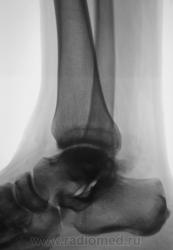

Пациент направлен на рентгенографию голеностопного сустава с диагнозом ДОА.

Похоже  на  остеохондропатию  блока  таранной  кости  +   ДОА.

Посттравматический артроз с кистовидной перестройкойлатерального мыщелка Субхондральное уплотнение исужение суст. щелей естьИ неконгруэнтность большеберцового эпифиза к таранной маленько просматривается?